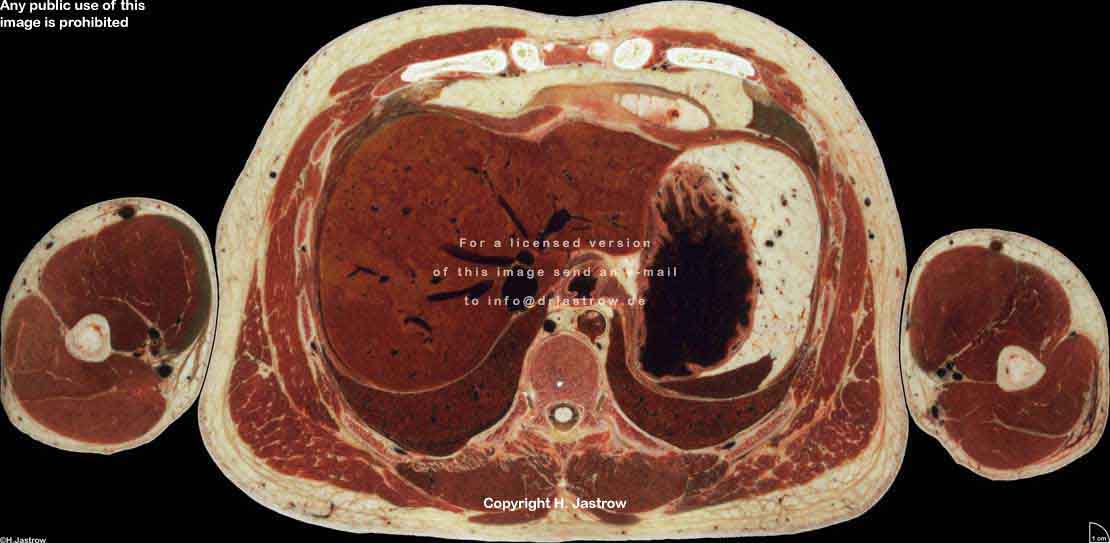

Visible Human male: Sectio transversalis 1498

CT

NMR

Pd                          / T2 \                         T1